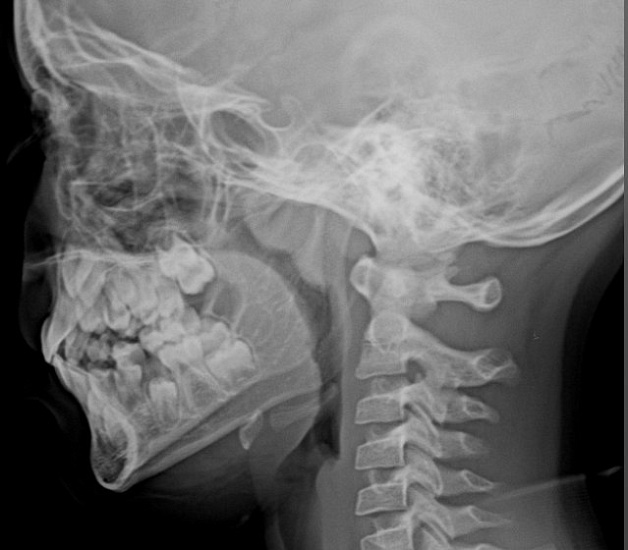

Рентгенография носоглотки – важный метод прицельного исследования, который позволяет оценить состояние носоглотки и ее просвет.

Диагностическая услуга выполняется в одной проекции.

Показания для проведения рентген носоглотки:

• нарушение носового дыхания;

• воспалительные процессы, деформации и травмы носоглотки;

• подозрение на наличие аденоидных вегетаций.